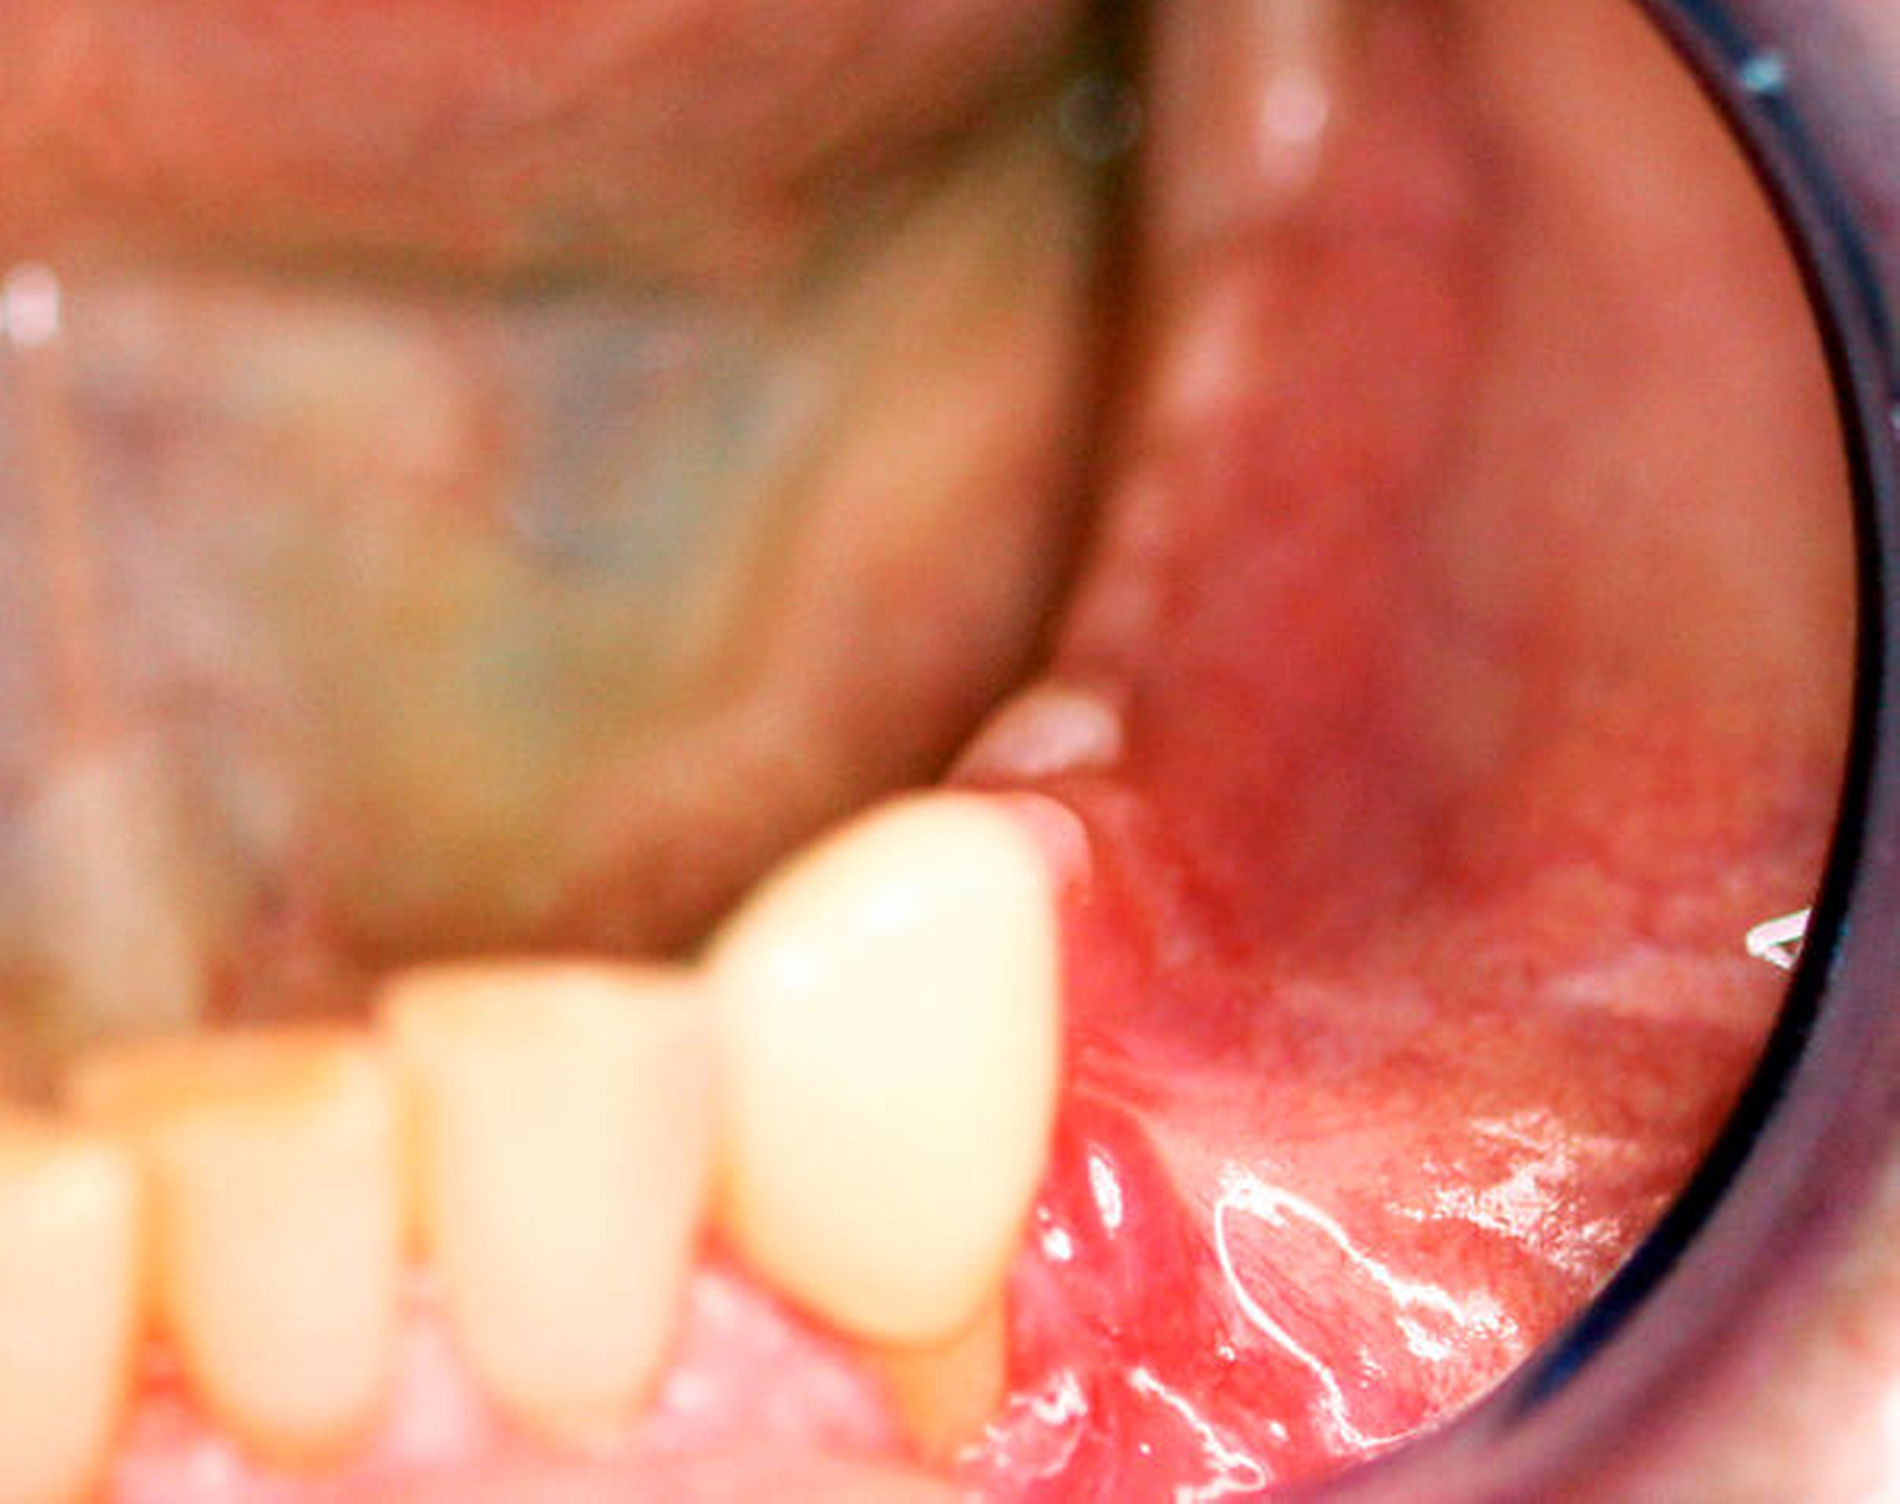

Aufgrund der seit einer Woche bestehenden Beschwerdesymptomatik mit Schmerzen im Bereich des linken Unterkiefers zeigte sich ein reduzierter Allgemein- und Ernährungszustand. Extraoral zeigte sich eine ausgeprägte, weiche Schwellung paramandibulär links. Der Unterkieferrand war zu jedem Zeitpunkt durchtastbar. Es zeigte sich eine Anästhesie im Versorgungsgebiet des Nervus mentalis links. Intraoral präsentierte sich eine Schwellung im Vestibulum sowie eine geringe Schwellung im Mundboden, ein Wurzelrest 34 sowie eine negative Sensitivität auf Kälte an den Zähnen 33 und 32. Im Oberkiefer zeigte sich ein prothetisch suffizient versorgtes Gebiss. Auch intraoral bestand eine Anästhesie im Versorgungsgebiet des Nervus mentalis links.

Der intraoperative Situs zeigte nach Abklappen des Mukoperiosts die Zugangskavität der alio loco durchgeführten Wurzelspitzenresektion. Der Wurzelrest 44 ist hierbei noch in situ (Abbildung 5).

Nach der Entfernung des Wurzelrests 44 wurde der Nervus mentalis am Foramen mentale dargestellt und aus dem umgebenden Weichgewebe frei präpariert (Abbildung 6). Aus der Resektionshöhle und nach Entfernung der vestibulären Knochenlamelle auch aus dem Unterkieferkörper konnte anschließend der Sealer samt der extrem weichen Spongiosa entfernt werden. Die Lage der radiologisch dichten Verschattung im krestalen Bereich regio 36 konnte ebenfalls lokalisiert und problemlos entfernt werden. Bei dem Fremdkörper handelte es sich vermutlich um einen Amalgamrest (Abbildung 7).